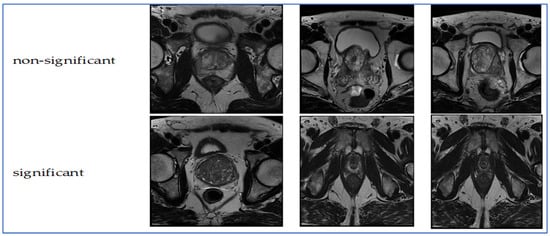

The TPP dataset comprises 1528 prostate MRI images captured in the transverse plane. The images and their classifications originate from the PROSTATEx Dataset and Documentation. The purpose of this dataset is to train a CNN known as Small VGG Net, enabling the classification of new images into clinically significant and clinically non-significant categories for an undergraduate thesis in systems engineering at the Autonomous University of Bucaramanga (UNAB). The images were collected from 64 patients, ensuring each had a single prostate MRI finding for improved training accuracy. The images were converted from DICOM format to JPEG. Image quality was verified through radiologist-reviewed coordinates and metadata, ensuring precise lesion localization and anatomical accuracy. The inclusion criteria required MRI exams to have complete multi-parametric sequences and validated lesion labels. Cases with missing sequences or poor image registration were excluded. The images were divided into two groups using a retention method: 30% for validation and the remaining 70% for training. Consequently, there are two categories (significant and non-significant) further split into training (70%) and validation (30%) groups [20,21]. Figure 1 presents samples from the TPP dataset.